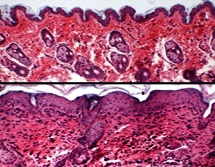

L'eczéma atopique, aussi appelé dermatite atopique, est une dermatose inflammatoire, caractérisée par des périodes de poussées de plaques rouges. L'équipe de dermatologues et cardiologues de la Brown (Providence, US) a analysé les dossiers de 259.119 adultes âgés de 30 à 74 ans participant au programme Canadian Partnership for Tomorrow Project pour vérifier une hypothèse récente : les personnes souffrant de dermatite atopique (DA) seraient beaucoup plus susceptibles de développer des troubles cardiovasculaires. 21.379 participants, soit 8,4% étaient atteints de DA. 52.787 cas d'hypertension artérielle, 12.739 diagnostics de diabète de type 2, 4.390 crises cardiaques et 2.235 AVC ont été signalés par les participants à l'inscription. Les chercheurs ont pris en compte les facteurs de confusion possibles, dont l'âge, le sexe, l'origine ethnique, l'indice de masse corporelle, le tabagisme, la consommation d'alcool, le sommeil, l'activité physique et l'asthme.